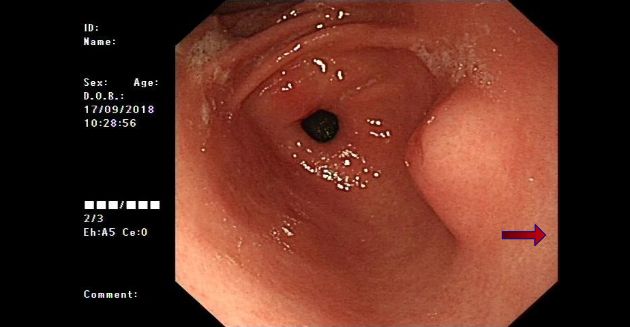

2018?, ??? ? ??? ??? ?? chronic gastritis, ??? gastric antrum?? lesser curvature? submucosal bulging mass? ??? ??? ?????. (?? 1).

2019?, ??? ??? ???? ??? gastric antrum?? lesser curvature? submucosal bulging mass? ?????? submucosal ectopic pancreas? ???????. (?? 2)